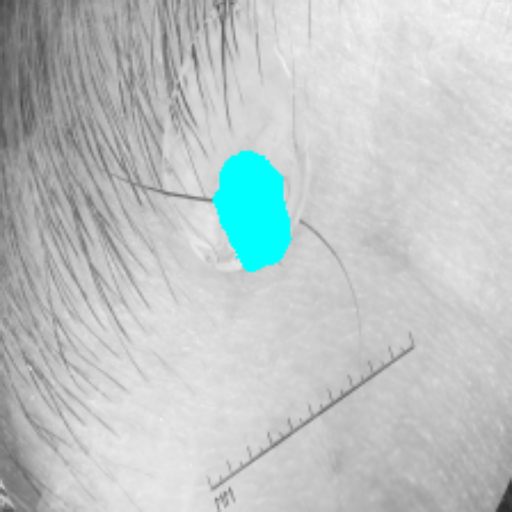

For binary segmentation tasks, Tables 5 and 6 demonstrate that our approach surpasses SOTA methods in segmenting skin cancer, glands, and multi-organ nuclei across the ISIC17, GlaS, and MoNuSeg [38] datasets. Specifically, MambaCAFU-V1 outperforms U-Net by 4.67% and the best comparison method, PVT-EMCAD-B2, by 0.31 in DSC on the ISIC17 dataset. Additionally, MambaCAFU-V0 and MambaCAFU-V1 achieve the second-best and best performance, respectively, with MambaCAFU-V1 outperforming the best SOTA method by 2.56% and 2.23% on the GlaS and MoNuSeg datasets, respectively.

Figure 3 presents a qualitative comparison of segmentation performance on examples from the Synapse, BTCV, ACDC, and ISIC17 datasets. The first two examples (from Synapse) highlight variations in segmentation performance among U-Net, TransUnet, Mamba-Unet, and Swin-Unet. While Swin-Unet performs well in the first example, its performance decreases in the second example, particularly in segmenting the organ highlighted in blue. Additionally, it misclassifies background regions as the class highlighted in orange. In contrast, our approach demonstrates high robustness in segmenting all classes accurately and aligning well with the ground truth masks.

Across BTCV, ACDC, and ISIC17, the comparison methods exhibit varying performance depending on the task and class. For instance, Mamba-Unet struggles to segment multiple organs in BTCV, even misclassifying certain classes as others. In the ACDC dataset, both TransUnet and Mamba-Unet perform poorly in segmenting the three classes. In the last column (ISIC17), Swin-Unet oversegments the skin lesion compared to the ground truth. Unlike the comparison models, our approach consistently delivers effective segmentation across different tasks and datasets.

These qualitative findings further reinforce the quantitative results presented in the experimental section, demonstrating the effectiveness of our MambaCAFU model in handling binary and multi-class segmentation across diverse medical imaging modalities and tasks.

Slice GT Unet TransUnet Mamba-Unet Swin-UMamba MambaCAFU-V1

Figure 3: Visual comparison of segmentation examples from Synapse (first two examples), BTCV (3-4 examples), ACDC (5th example) and ISIC17 (last example). Columns: input slice, ground truth, Unet, TransUnet, Mamba-Unet, Swin-UMamba, and MambaCAFU-V1.